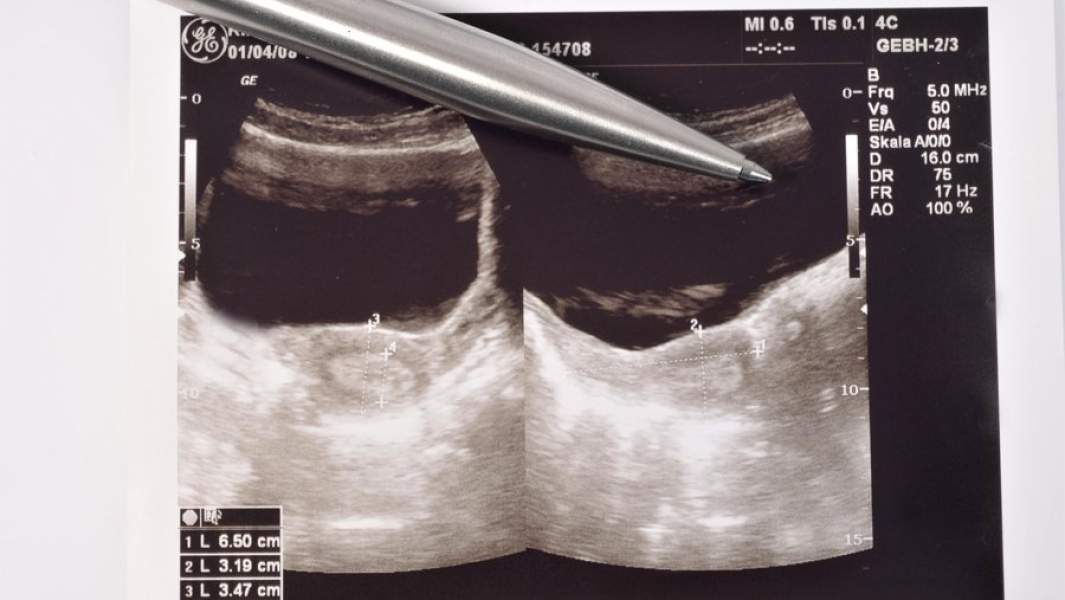

Ученые из Китая опубликовали научную работу, в которой сообщили, что коронавирус может инфицировать яичники, матку, плаценту и другие органы женской репродуктивной системы, так как на поверхности их клеток присутствуют белок ACE2 — входные ворота для патогена. По мнению авторов, SARS-CoV-2 потенциально способен приводить к бесплодию. Российские специалисты подтверждают такую возможность: вирусов, приводящих к проблемам с фертильностью, известно много. Однако для SARS-CoV-2 это пока лишь гипотеза. Необходимо наблюдать за здоровьем переболевших женщин, а также беременных, чтобы сделать более точные выводы.

Специалисты предупреждают о потенциальном риске развития бесплодия у переболевших уханьской пневмонией пациенток. В начале мая ученые из департамента физиологии Медицинского университета Цзинина (Jining Medical University) опубликовали статью, в которой приведены данные о возможном влиянии заражения коронавирусом на репродуктивную систему женщин. Они предполагают, что патоген может проникать в органы мочеполовой системы из-за того, что на их клетках в большом количестве представлены рецепторы ACE2 (или АПФ2 — Ангиотензинпревращающий фермент 2 — входные ворота для SARS-CoV-2. — «Известия»). Через них инфекция попадает в клетки организма. Как сказано в статье, в науке уже представлено много данных о наличии этого белка в печени, почках, ЦНС, а не только в легких. Однако данных о женской половой системе пока крайне мало.

Исследователи проанализировали научную литературу о наличии таких рецепторов у женщин. Они пришли к заключению, что ACE2 регулируют развитие фолликулов и овуляцию, а также влияют на изменения в ткани эндометрия и развитие эмбриона. Вывод таков: заражение через эти структуры коронавирусом способно нарушить репродуктивные функции женщины.

узи

Фото: Global Look Press/Ulrich Niehoff

«SARS-CoV-2 может инфицировать яичники, матку, влагалище и плаценту через повсеместную экспрессию ACE2», — сказано в выводах этой работы. В конечном счете это угрожает пациенткам бесплодием. Также возможны нарушение менструального цикла, респираторный дистресс-синдром у плода, если женщина беременна, и другие патологии. В связи с этим, медики предупреждают о необходимости последующего наблюдения и оценки фертильности переболевших женщин уже после выздоровления.